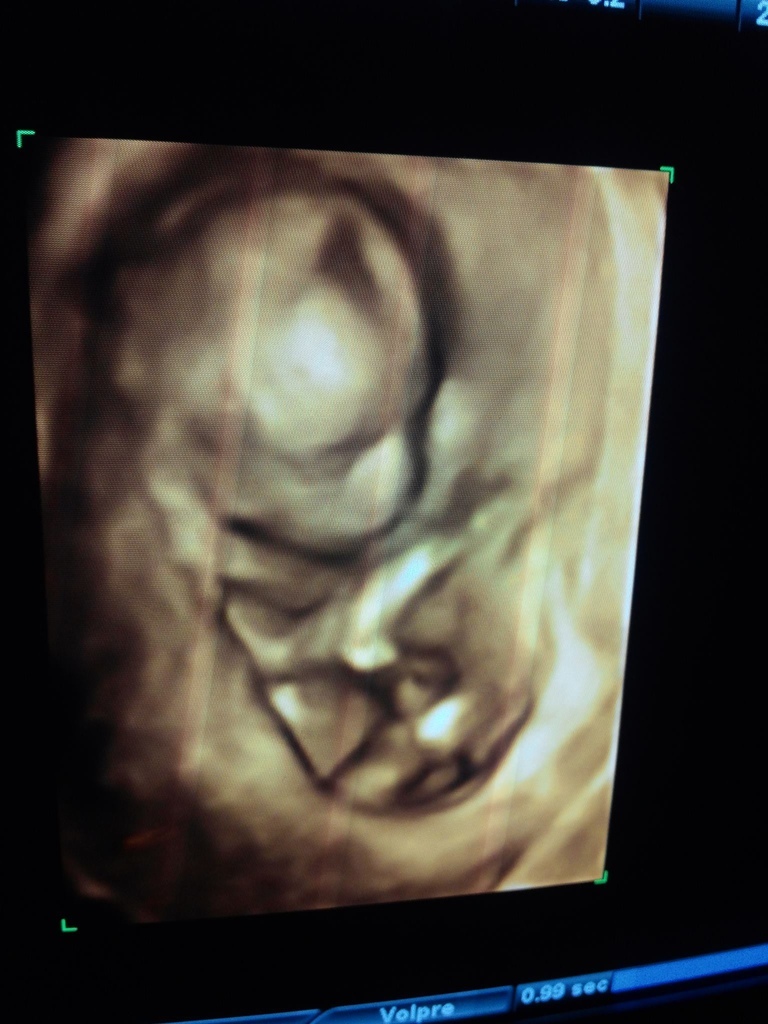

一路走來。以前只需要每個月,緊張一次,有中或是沒中?懷孕之後,每天都緊張。從初期的有沒有流血,要不要做羊穿?到中期的肚子緊!(PS:一開始還不知道什麼是肚子緊的感覺,我只知道我吃太撐肚子很撐而已。)到後期的每天擔心肚子緊,子宮收縮,早產產兆,何時會生?真的是天天照三餐操煩。老婆從本來比我還會走路的耐操身體狀況到後面,只短短走路到樓下就會喘氣,肚子蹦。舉步維艱呀…這個懷胎期間真的是辛苦了。尤其又是高齡產婦。